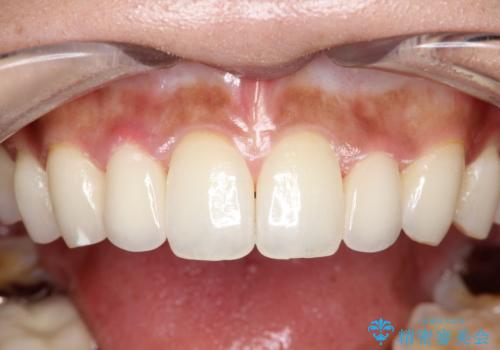

【オールセラミッククラウン】矮小歯の治療

- 矯正治療で配列した矮小歯をオールセラミッククラウンで修復治療を行いました。

すごく自然な仕上がりになり満足していただきました。

オールセラミッククラウンは、隣の歯に合わせて色調を調整することができるため非常に綺麗に仕上がります。